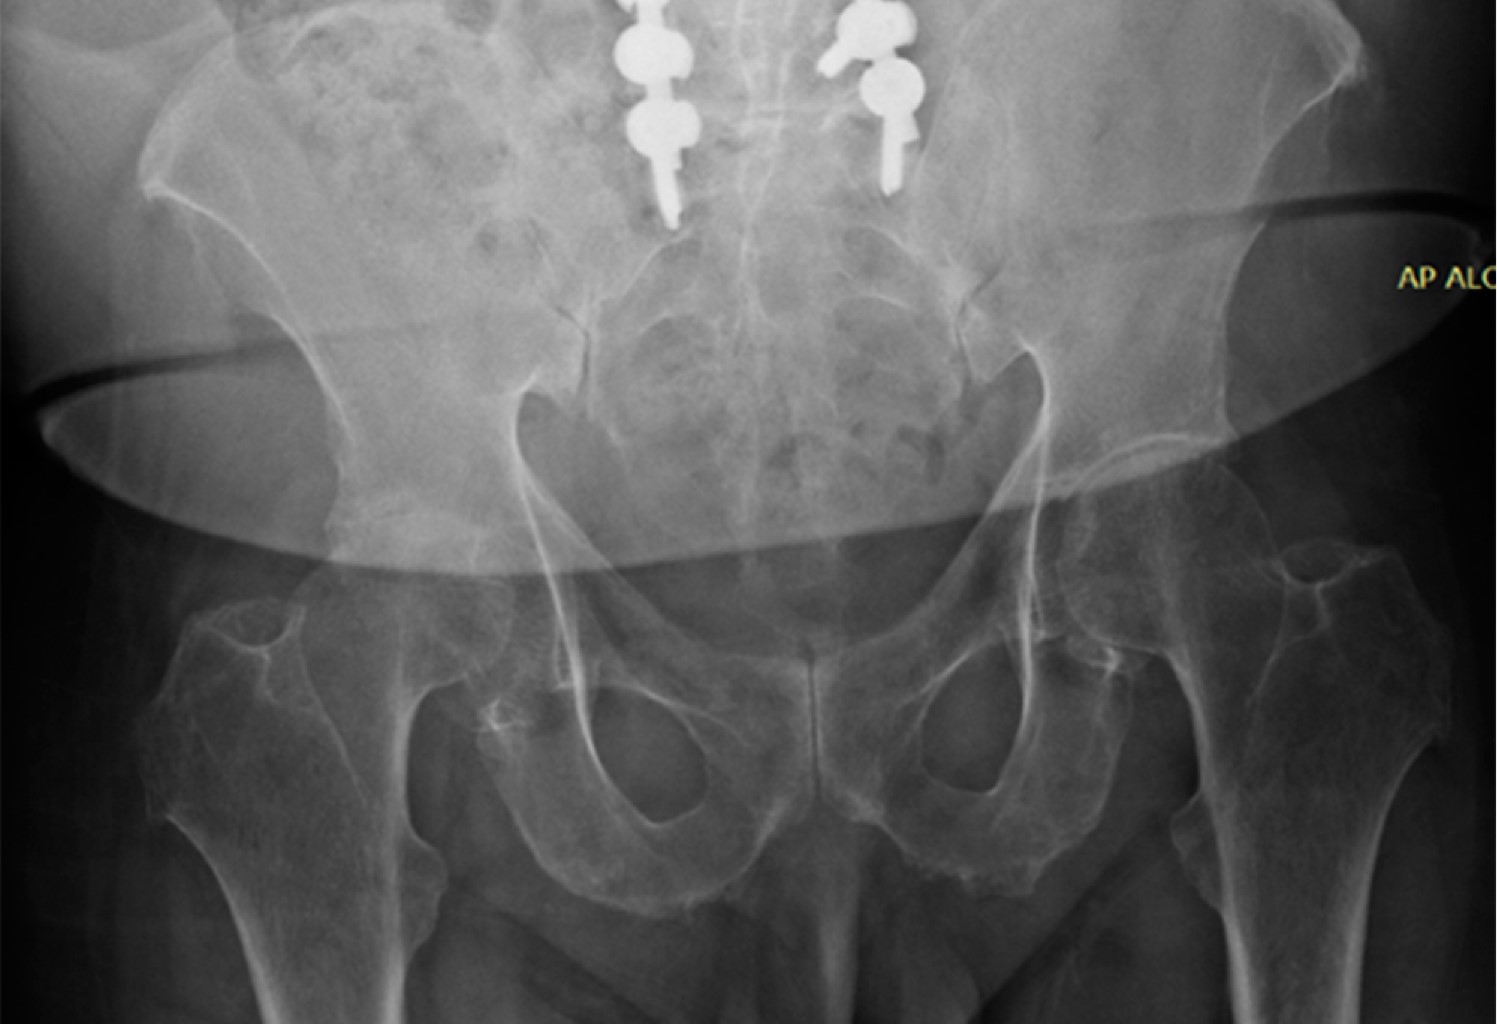

Alkaptonuria: evolution and course of the disease towards ochronotic arthropathy. Series of cases managed with joint replacement

Introduction: alkaptonuria is a very rare metabolic disease with autosomal recessive inheritance due to HGA oxidase deficiency. Classically described and diagnosed in the third to fourth decade of life, affecting both men and women; Its diagnostic impression is clinical based on the blue/black coloration of the conjunctivae, however it is confirmed by the specific analysis of the enzyme in the urine, to date there is no cure and its treatment is palliative and symptomatic. Material and methods: descriptive, observational, case series study, the primary objective of which is to describe the progression of the disease and its involvement in the musculoskeletal system. Results: two clinical cases are presented in women and men in which the broad clinic is illustrated, its progressive advance and the different alterations that it can generate in the musculoskeletal system. Conclusions: alkaptonuria is a rare disease which leads to a severe secondary arthropathy, currently without a specific management which is based on treating the symptoms, in its final stages joint replacements are a management option with satisfactory results for the relief of pain.

Figure 4